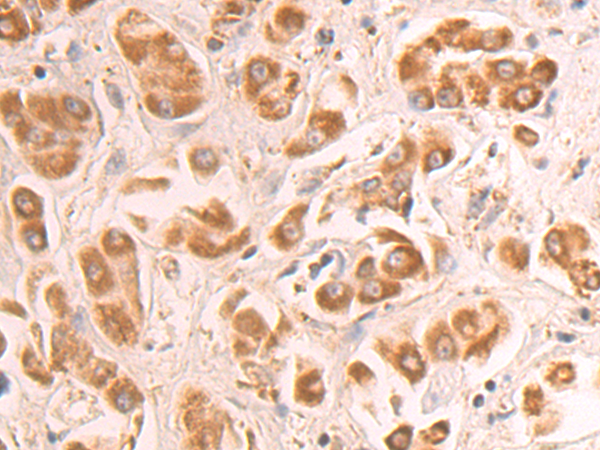

分类: 科研抗体货号: P07978别名:应用: WB,IHC反应种属: Human